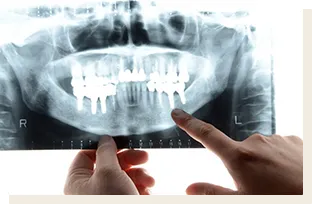

1 歯科用CTなどを活用した正確な診査診断

インプラント治療成功のポイントは「口腔衛生環境」、「身体の健康状態」、「骨の状態(骨の幅、深さ、密度)」、「インプラントの埋入位置」、「担当するスタッフの技術や評判」、「院内の衛生環境」等様々あります。

当院では、歯科用CTによる一般的なレントゲン写真よりも高い精度での検査により、患者様の顎の状態を詳細に把握することで、手術の成功率を高めるとともに患者様の治療時と治療後の痛みの軽減にも役立ちます。

歯科用CT 恵比寿南DENTAL

歯科用CT

歯科用CTは、従来の2次元のレントゲン装置とは異なり、3次元の立体画像を撮影可能にする装置で、精度の高い診査診断検査や精密歯科治療を行う際には欠かせない機器です。

従来の2次元のレントゲン撮影による画像では見ることができない口腔内を3次元的に把握できることで、歯や歯周組織、顎の骨やその中にある神経や血管の位置まで正確に把握することができます。

当院では、歯科用CTを完備しておりますので、歯周病治療、根管治療、インプラント治療や親知らずの抜歯など、精度の高い診査診断が求められる治療も安全に受けて頂けます。